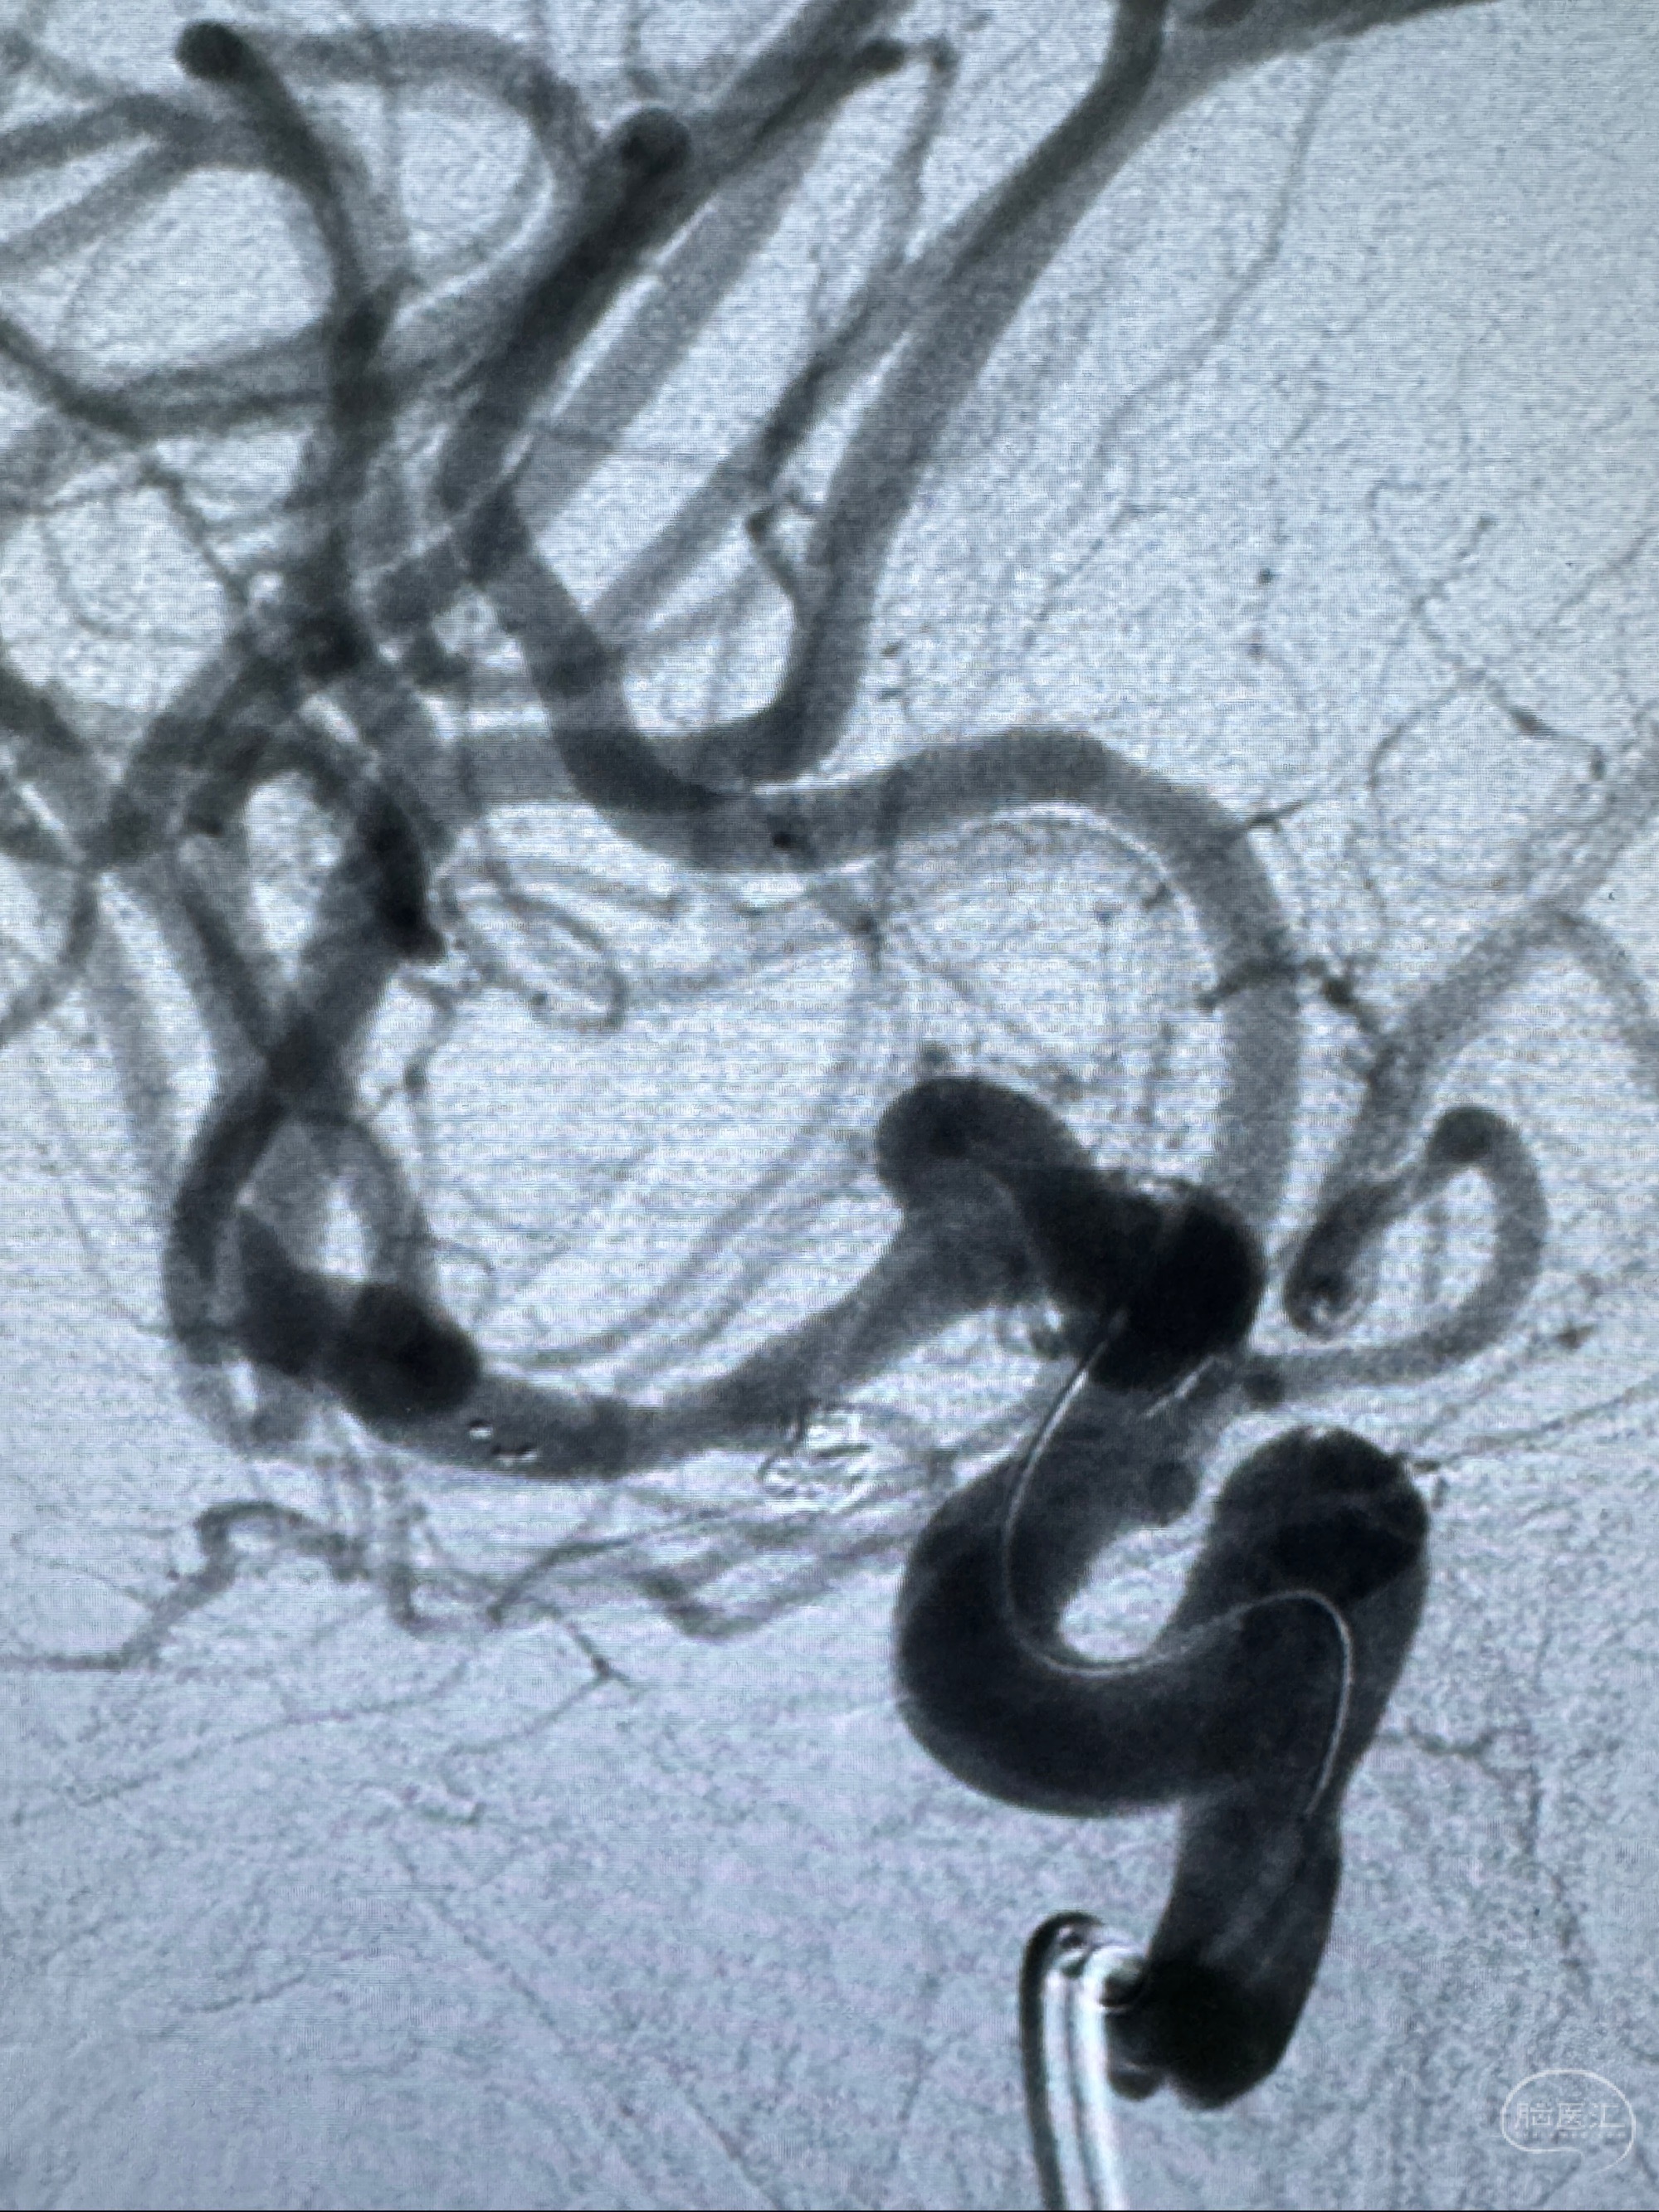

2023-11-24DSA:右侧大脑中动脉下干起始部动脉瘤,约2.3*2.5mm,形态规则

2023-12-04全麻下行支架辅助治疗

S-AB4-20mm

麻醉苏醒佳,遵嘱动作

术后即刻CT